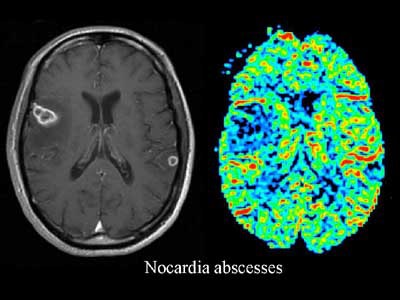

Left: contrast-enhanced T1-weighted image shows multiple rim-enhancing masses in both hemispheres. The MR features are indeterminate for abscess or tumor. Right: rCBV map shows regions of decreased blood volume corresponding to rim-enhancing lesions seen on image at left. The lesions proved to be nocardial infection.

On an rCBV map the normal gray matter was depicted in reds and yellows. The abscesses had lower rCBV values than those of normal gray matter, and were depicted in green and dark blue.